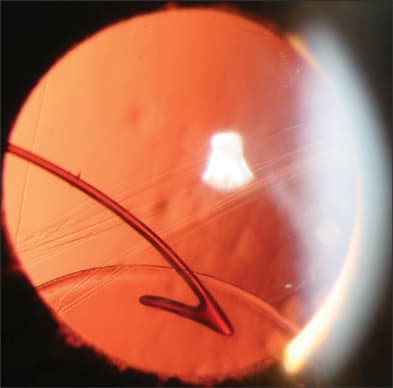

The majority of patients with posterior IOL dislocations are treated surgically, by either a limbal or a pars plana approach. If the IOL is still supported to some degree by the capsular remnants, an anterior-segment (limbal) approach may be considered (Figure 2). However, when the patient is supine on the operating table, the IOL frequently falls further posteriorly, making a limbal approach more difficult. Pars plana vitrectomy (PPV) techniques offer several advantages to a limbal approach, including more complete and controlled removal of formed vitreous, better access to the posterior vitreous cavity and better ability to address potential intraoperative complications, such as retinal tear, suprachoroidal hemorrhage or progressive IOL dislocation into the posterior vitreous (Figure 3).

Figure 2. Subluxed posterior chamber intraocular lens, partially supported by capsular remnants.